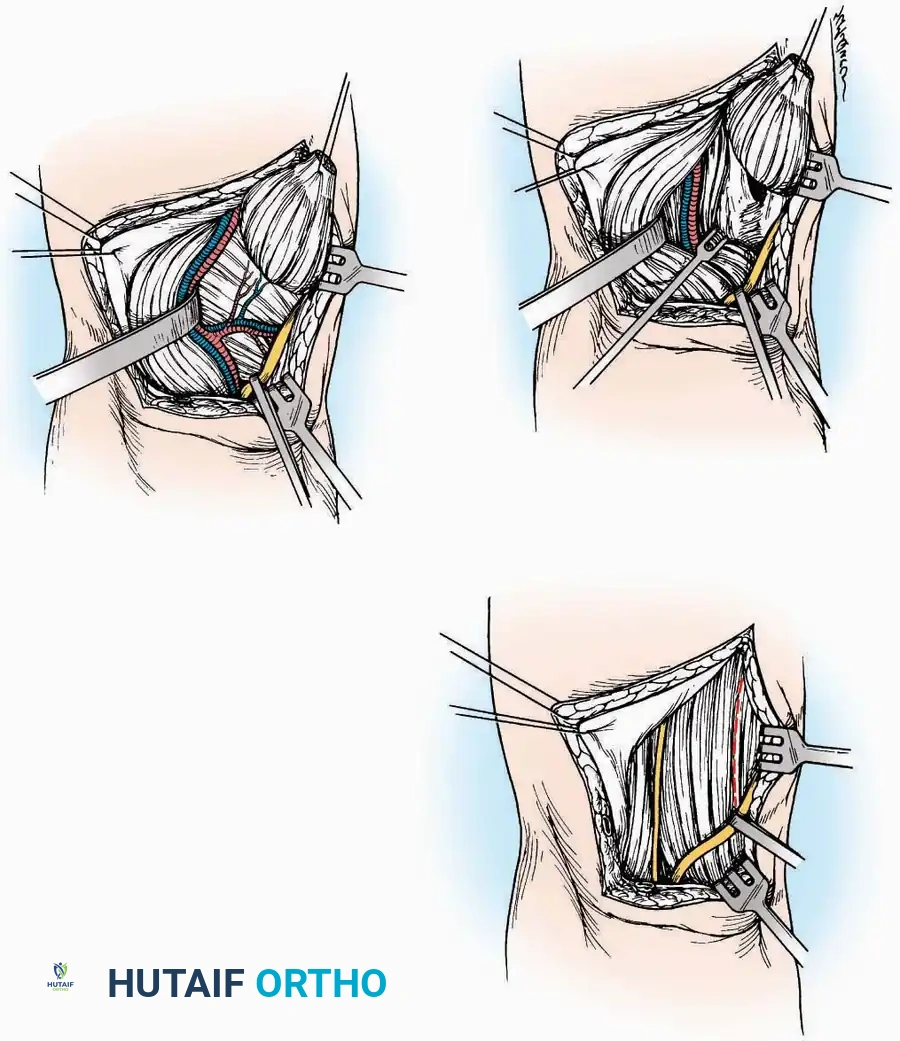

Surgical Technique:

* Incision: Begin the incision on the lateral margin of the Achilles tendon near its insertion. Extend it distally to a point 4 cm inferior and 2.5 cm anterior to the lateral malleolus. (For trauma, a classic L-shaped extensile incision is often used, dropping straight down anterior to the Achilles, then curving gently toward the base of the 5th metatarsal).

* Superficial Dissection: Divide the superficial and deep fasciae. It is imperative to create a "full-thickness" flap containing skin, subcutaneous fat, and periosteum to prevent flap necrosis.

* Nerve Protection: The sural nerve crosses the proximal and distal limbs of this approach. It must be identified and protected within the anterior flap.

* Deep Dissection: Isolate the peroneal tendons (longus and brevis). Incise and elevate the periosteum below the tendons to expose the lateral wall of the calcaneus.

* Tendon Management: If severe deformity or infection is present, the peroneal tendons may be divided via Z-plasty and repaired at the conclusion of the case, though this is rarely necessary in modern fracture care.